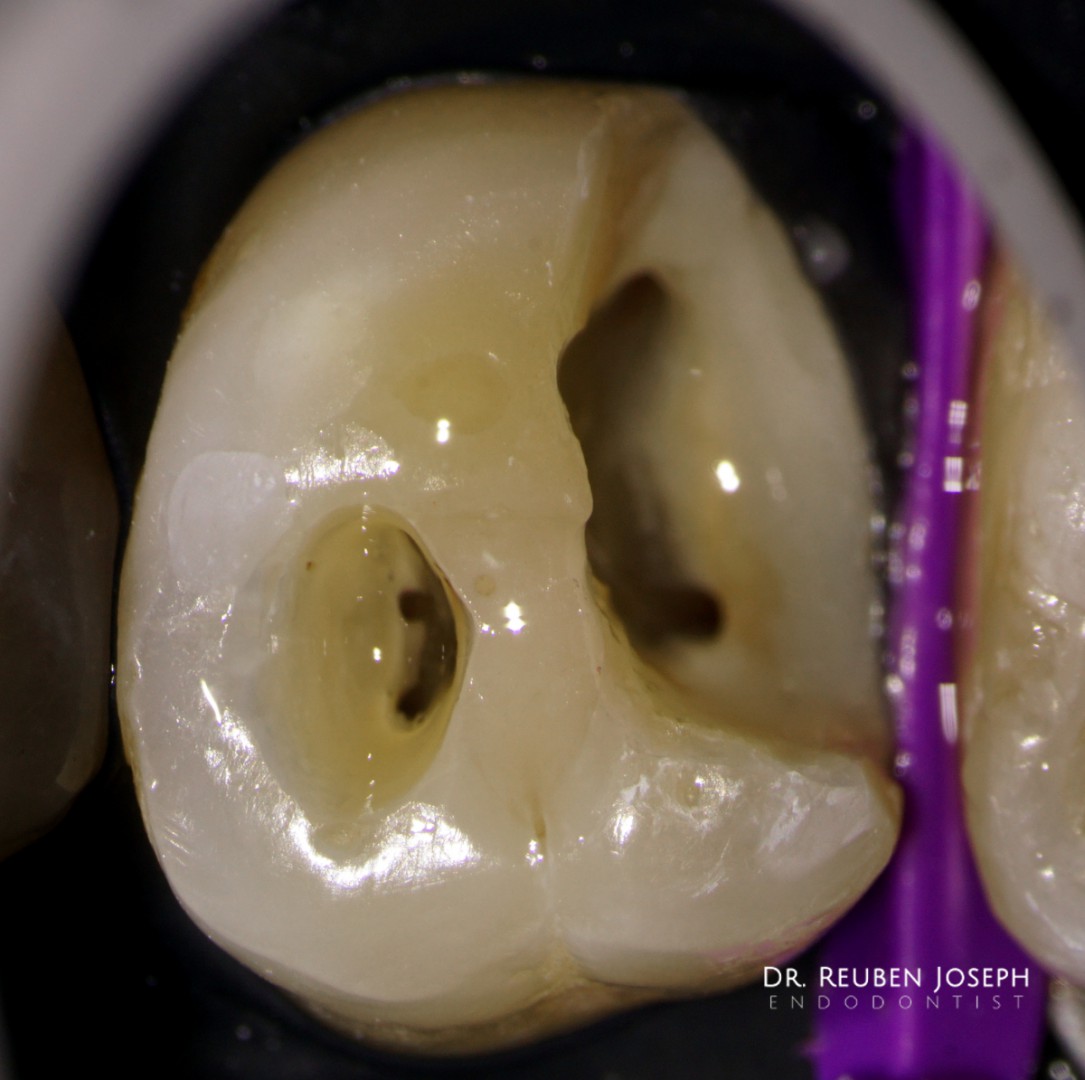

#14 RCT

Pre-op: Deep sub-gingival distal margin. Gingivectomy followed by margin elevation and isolation.

The usual shaping protocol and cleaning protocol. Obturated using WVC. Preserving the dentin bridge that extends buccal to lingual during post-endo prep might be a important consideration in this case.

This case highlights how critical dentin preservation is during RCT.